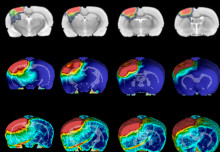

Participants in the TBI study will undergo assessments that include ultrasensitive fluid biomarker analysis, advanced MRI (including DTI, fMRI, and 7T high field strength MRI), tau PET, and advanced computerised cognitive assessment. The study will largely take place at the state-of-the-art rehabilitation facility at Stanford Hall, where the core ADVANCE Study is already based.